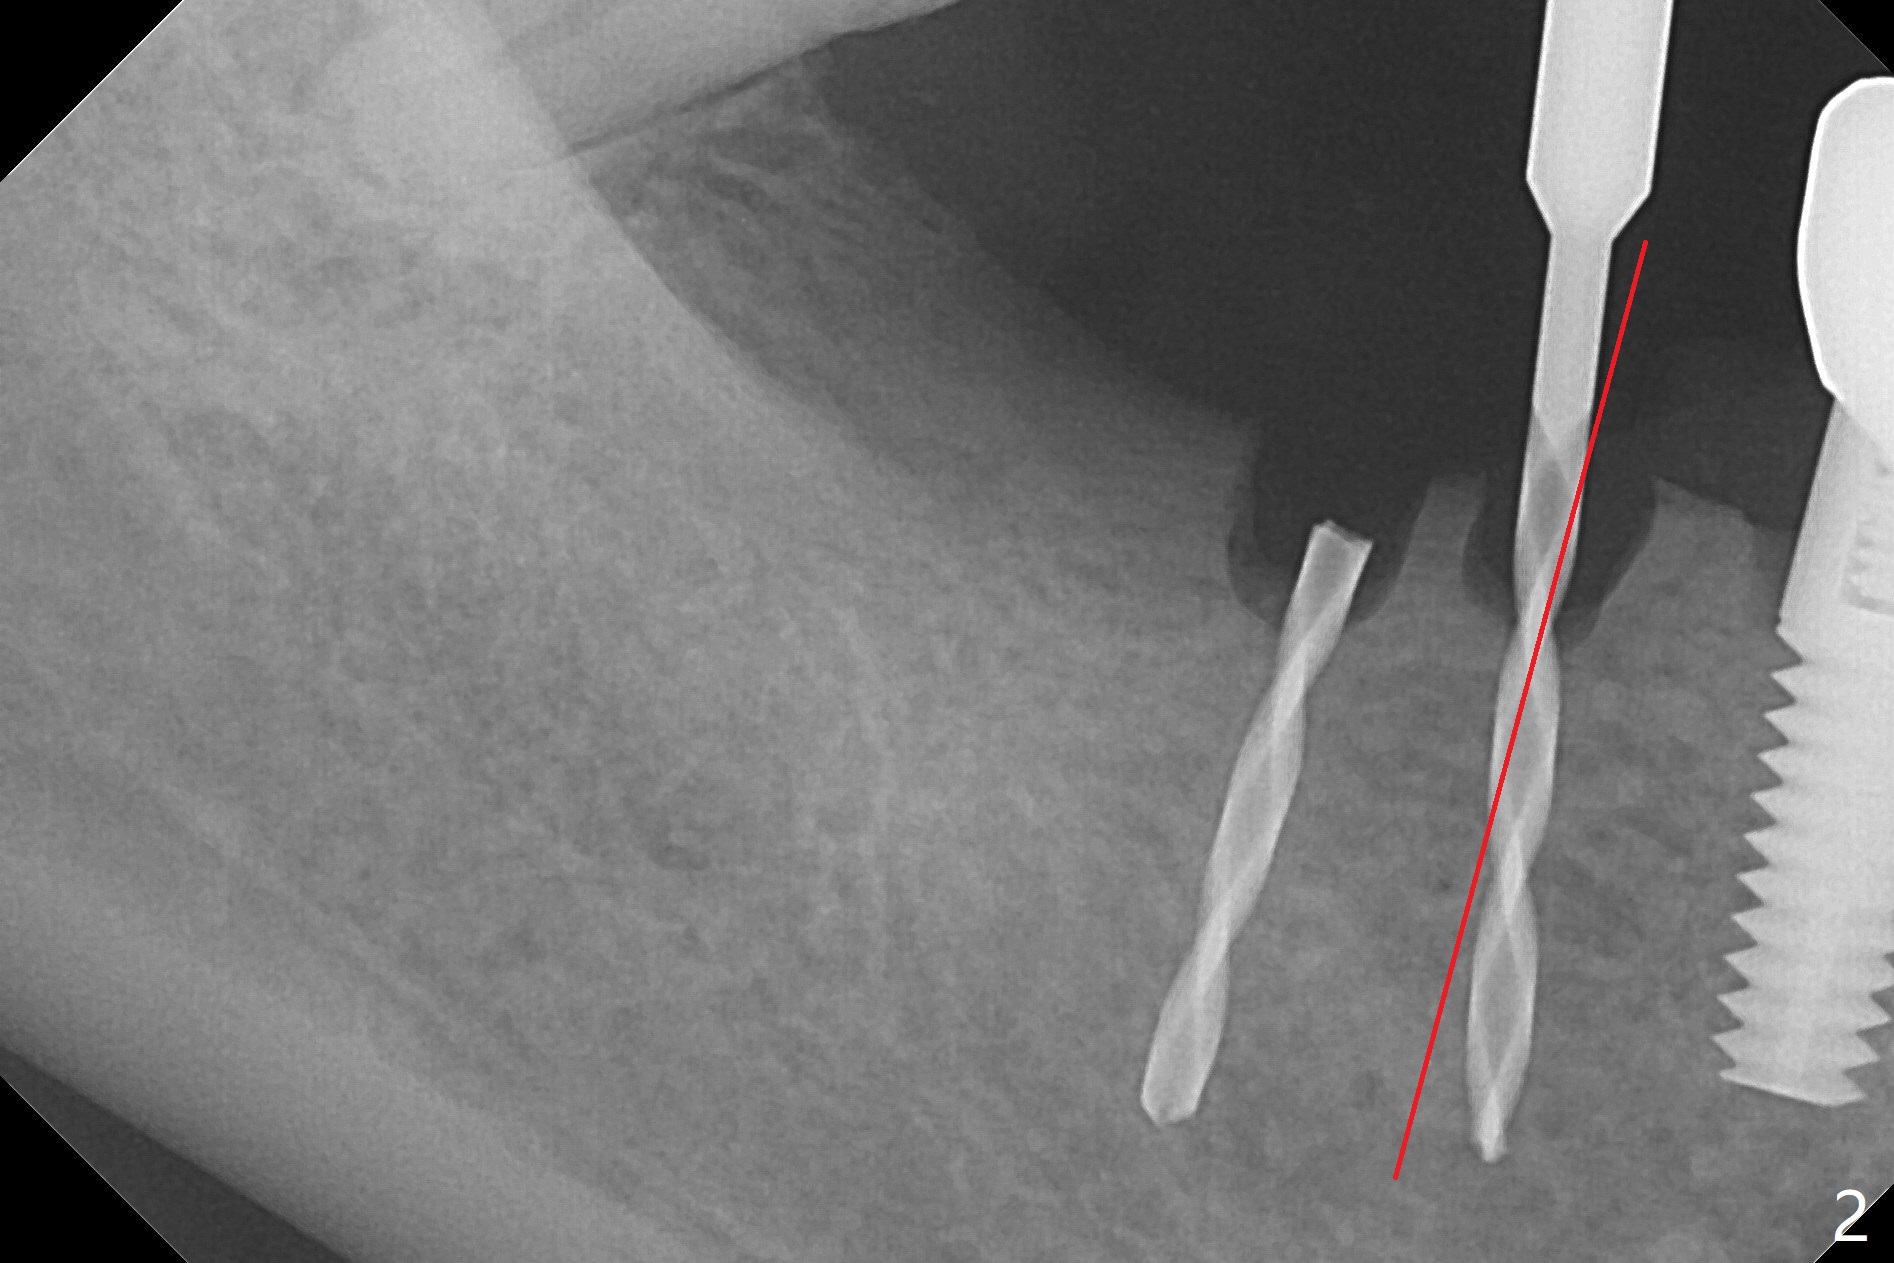

The edentulous ridge at #30 is narrow (Fig.1). After ridge reduction, osteotomy is initiated with 1.2 mm drill for 10 mm; the mesial osteotomy is to be changed (Fig.2 red line). Using a 1.2 mm drill placed in the distal osteotomy (Fig.3 D), the mesial osteotomy changes in trajectory with subsequent placement of a 2.5x10(4) mm 1-piece implant. Since the mesial implant is high in occlusion, the cuff of the distal implant is changed to be 2 mm (Fig.4 (shorter black line)). Panoramic X-ray is taken to show no violation of the Inferior Alveolar Canal (Fig.5 red dashed line). These two 1-piece implants are slightly lingually placed (Fig.6). The crestal bone around the implants resorbs without thread exposure 5 months postop (Fig.7). Impression is taken for a splinted crown (Fig.8-12). There is no metal show around the 2.5 mm 1-piece implants 6 months postop (advantage) vs. that at #28 and 29 (Fig.13). Bitewing is taken post cementation to determine whether residual cement is present (Fig.14). There is periodic swelling and pain in the lower right quadrant 2 years post cementation (Fig.15). In fact periimplantitis appears to have developed at #28 (Fig.16) with loss of the buccal bone (Fig.17,18). The buccal bone loss is less at #29 (Fig.19) and #20 (Fig.23) and no at #30 mesial and distal implants (Fig.20,21). A much smaller implant will be placed lingually at #28 immediate (Fig.24,25).